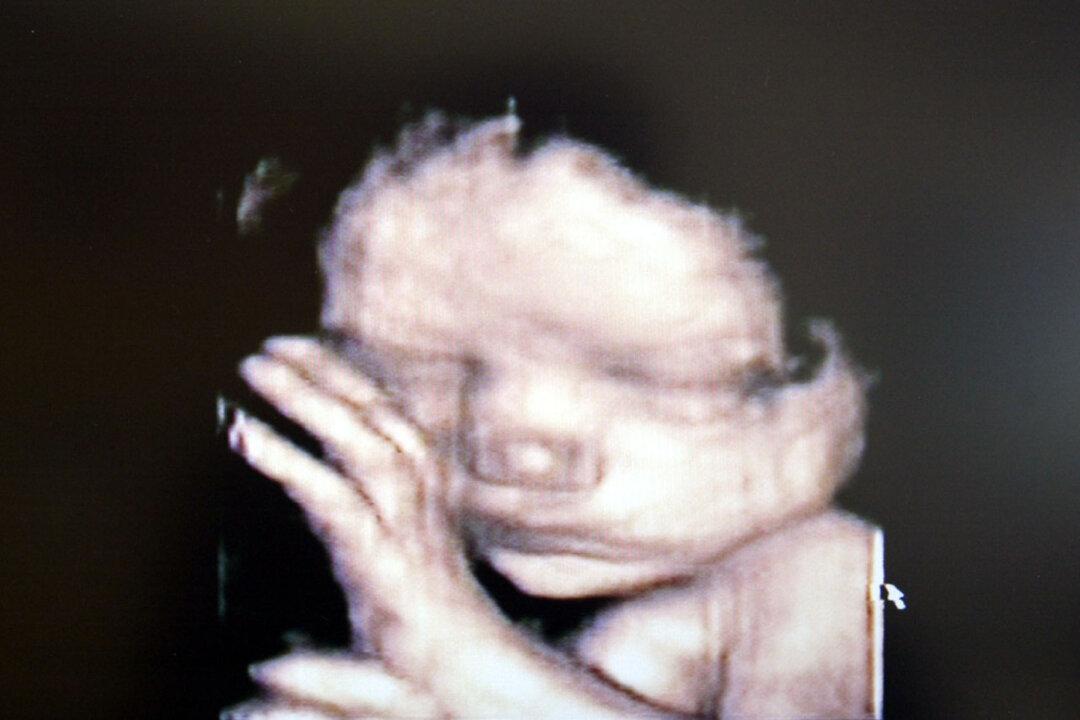

The Tennessee House of Representatives passed a bill on March 7 that would ban abortions in the state after the detection of an unborn baby’s heartbeat, which typically happens between six to eight weeks after conception.